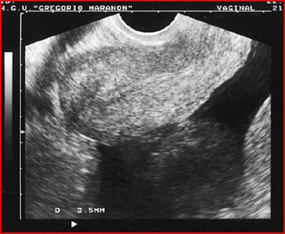

On the other hand, the literature reports cases of ovarian Burkitt lymphoma that were treated immediately by surgery, precisely because the diagnosis of lymphoma was not suspected. This is the case described in Szu-Ching Lu et al [10] who describe the appearance of ovarian Burkitt’s lymphoma in a 50-year-old woman. Unfortunately, the woman does not present with the common systemic symptoms of lymphoma such as fever, night sweats, nausea, vomiting or bladder symptoms. His Pap test was normal and on physical examination, as in the cases described previously, a pelvic mass of the size of approximately 20 weeks of gestation was revealed. The high resolution trans-vaginal ultrasound examination revealed a large and homogeneous abdominal mass measuring 10.8 x 8.7 cm extending from the uterus to the left ovary and the presence of a minimal content of free liquid (Figure17-18 ). Power-Doppler ultrasound showed no vascularity in the mass. All blood tests, including tumor markers, were normal before surgery.

Figure 17: Trans-abdominal ultrasound showing a large irregularly shaped echogenic pelvic mass. The mass measures 10.8 x 8.7 cm.

Figure 18: Trans vaginal ultrasound showing a large pelvic mass, extending from the right anterior wall of the uterus, with homogeneous echogenicity and some small anechoic areas within the mass.